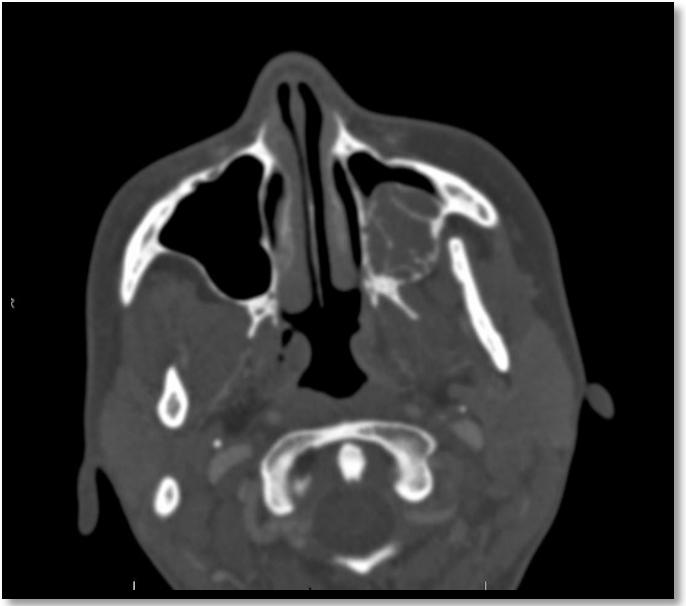

8.OdontogenicMyxoma:CaseReport (Pg.77-86)

MyxomaOdontogénica:ReportedeCaso

EvaChiang,DDS,MPH,LynnSolomon,DDS,MS,ElíasMorón,DDS,MPH,MHL